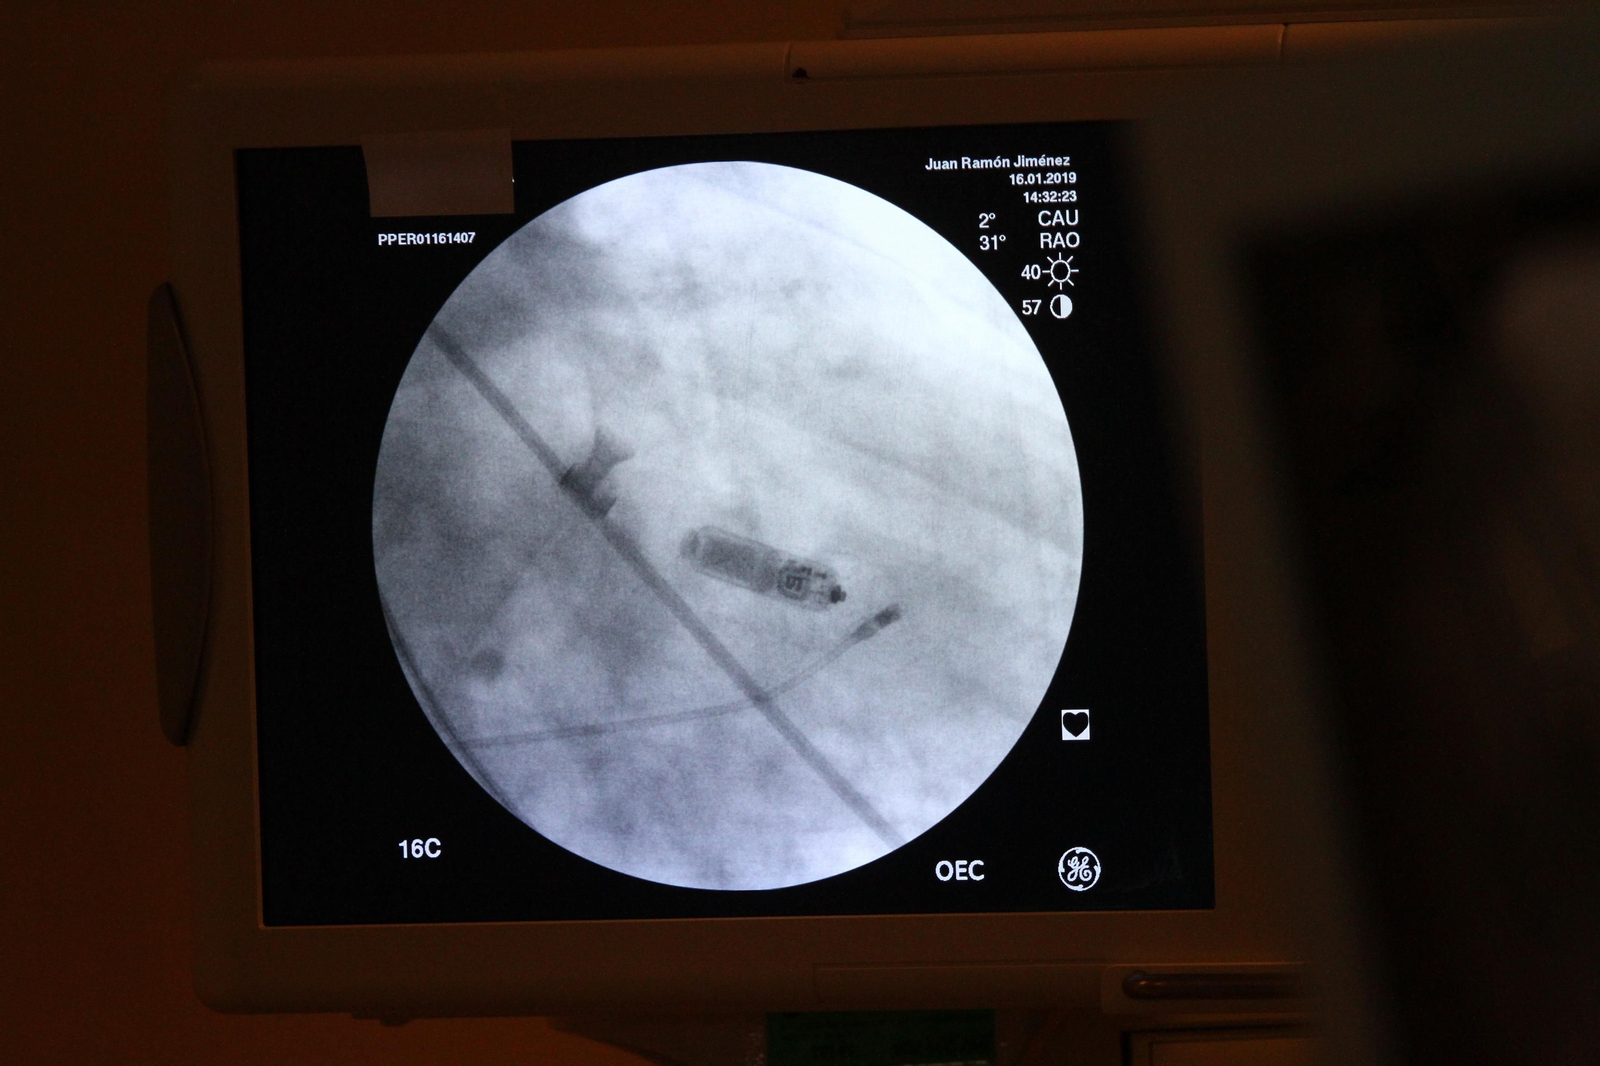

El Hospital Juan Ramón Jiménez implanta los dos primeros marcapasos sin cable en pacientes onubenses